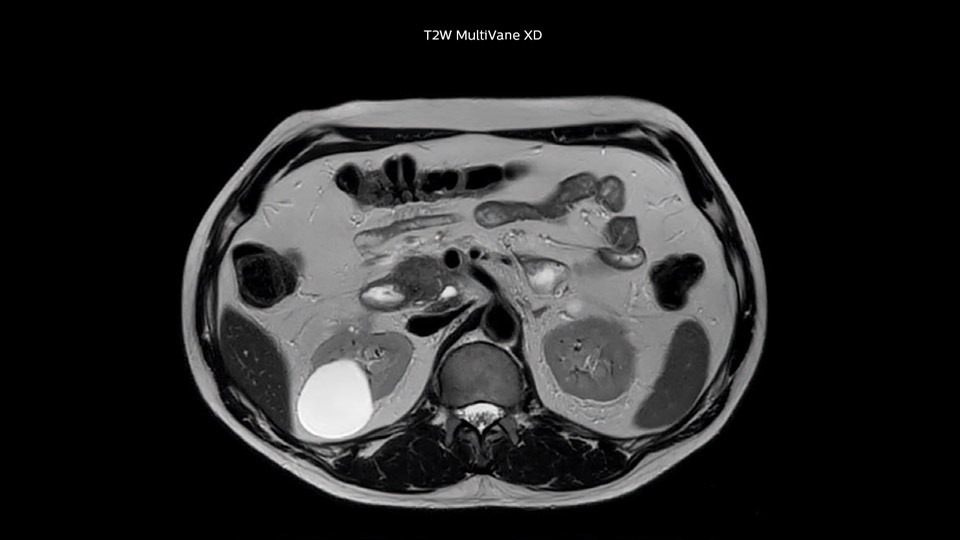

Comparison of liver MRI with and without MultiVane XD motion correction

In this example the image quality of the MultiVane XD images is evidently better than in the images without MultiVane XD. Ingenia 1.5T with dS Torso coil solution.

“We acquire one transversal high resolution T2-weighted sequence with 3 mm slice thickness, for example for pancreas or liver lesions. Then we also add a T2 fat suppressed MultiVane XD SPIR sequence. We perform these two routinely in our liver imaging. We use high dS SENSE factors to significantly shorten scan times to 2-4 minutes, which can improve our protocol; it’s a very robust scan.”